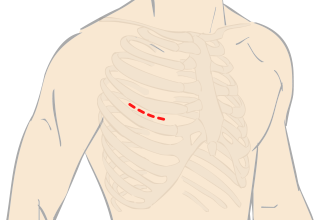

傷が小さく、感染症リスクが少ない内視鏡手術。体の負担を軽減し、手術後の回復を早めることができます。

体にやさしく、感染症リスクが少ない手術を行うために、低侵襲性小切開を採用。負担をなるべく減らすことを目指して、冠動脈バイパス手術を行います。

“ダビンチ”キーホール手術は、手術支援ロボット“ダビンチ(da Vinci Surgical System)”を用いたロボット手術です。開胸することなく、骨を切らず、数カ所のキーホールからすべての操作が遂行できるので、術中の出血が少なく、術後の痛みも軽く、また大きな傷が残らないため美容的にも優れています。従来のように人工心肺などを使用して遂行していた手術が“ダビンチ(da Vinci Surgical System)”の出現により劇的に変化し、術後経過や術中の体への負担が軽減できるようになりました。“ダビンチ(da Vinci Surgical System)”のような内視鏡手術の進歩は心臓だけでなく、すべての領域で目覚ましい発展を遂げています。現在では珍しいものでは無く標準の手術方法として認められる傾向にあり、新たなアプローチとして広い分野で採用されています。

手術支援ロボット“ダビンチ”を使用したロボット手術は、骨を切らずに小さな傷口のみでオペを行い、出血量・痛みの減少を実現します。早期の社会復帰が可能な手術です。

手術支援ロボットのダビンチによる手術や小切開手術が可能な場合がございます。ダビンチの手術は小さな3つの穴から手術を行うため従来の方法より痛みや傷の感染、出血量が軽減。

手術内容や時間は患者様の状態やご病気によって異なりますが、通常の小切開手術もダビンチを使う手術も平均2時間半から3時間ほどで完了いたします。